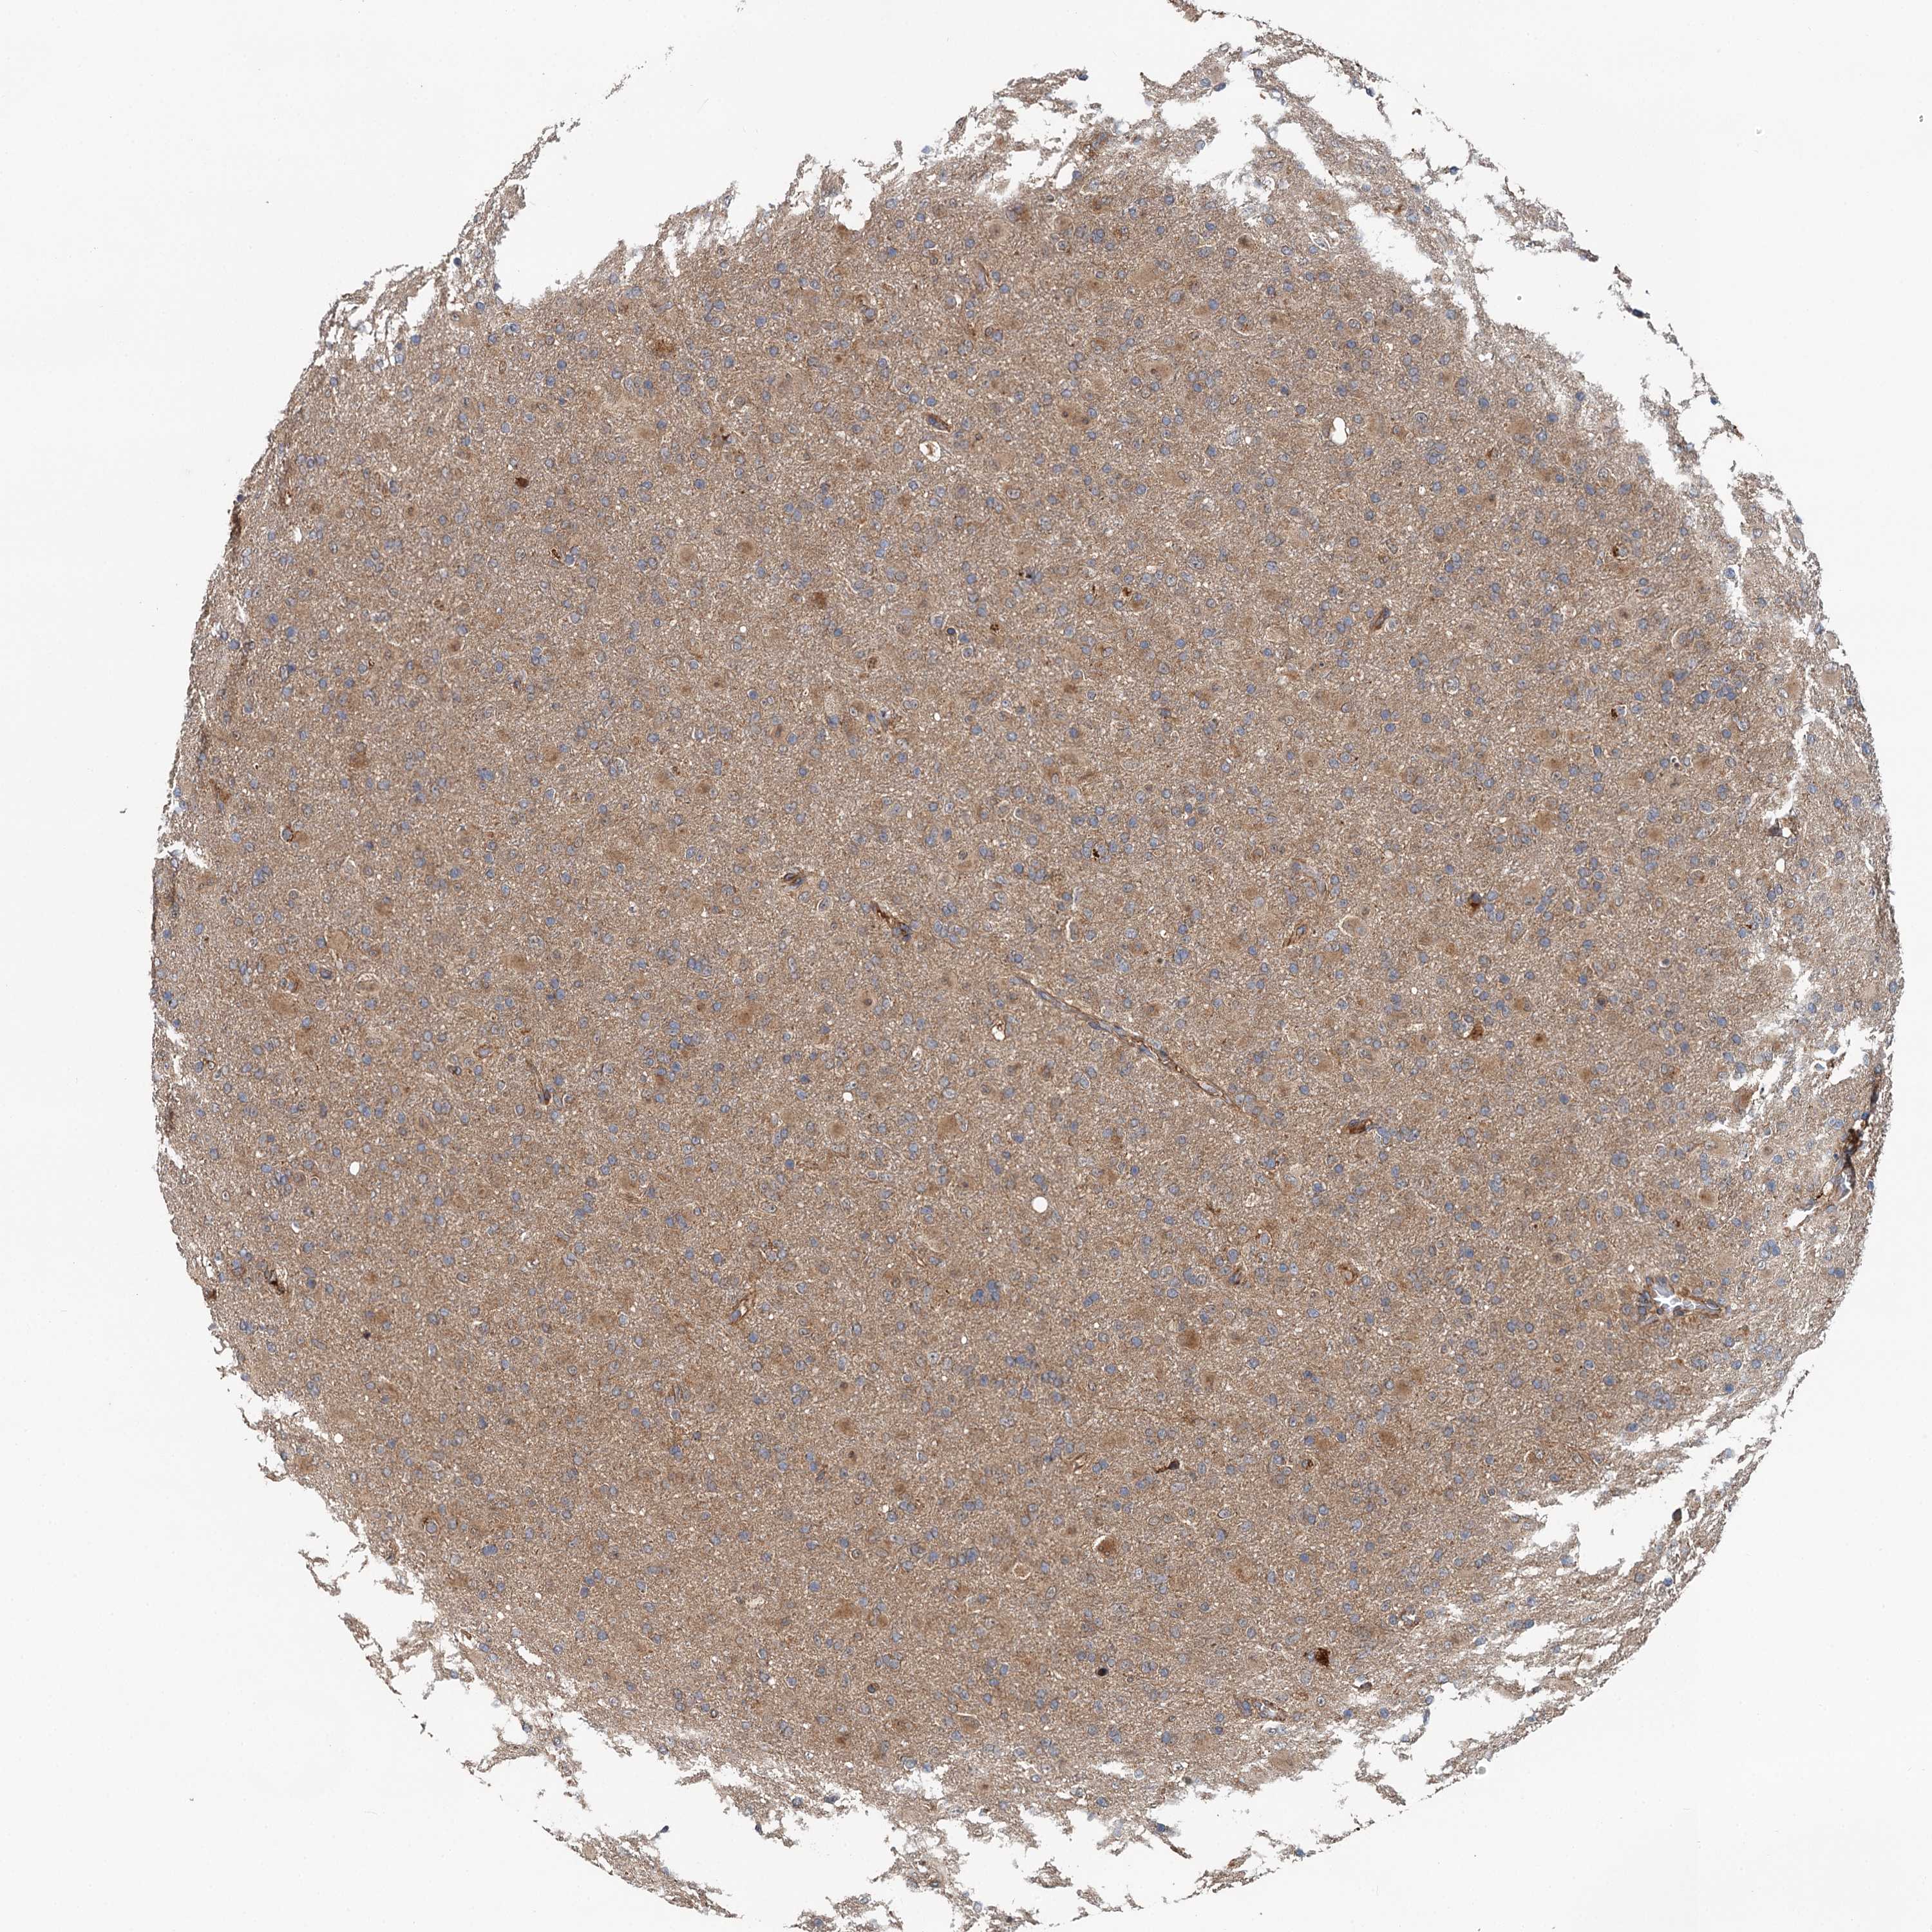

GLIOMA - Protein expressioni

A mouse-over function shows sample information and annotation data. Click on an image to view it in a full screen mode. Samples can be filtered based on level of antibody staining by selecting one or several of the following categories: high, medium, low and not detected. The assay and annotation is described here.

Note that samples used for immunohistochemistry by the Human Protein Atlas do not correspond to samples in the TCGA dataset.

Antibody stainingi

Antibody staining in the annotated cell types in the current human tissue is reported as not detected, low, medium, or high, based on conventional immunohistochemistry profiling in selected tissues. This score is based on the combination of the staining intensity and fraction of stained cells.

Each image is clickable and will lead to virtual microscopy that enables deeper exploration of all samples and also displays staining intensity scores, fraction scores and subcellular localization as well as patient and tissue information for each sample.

Antibody HPA014293

Antibody CAB037160

Staining

High

Medium

Low

Not detected

Intensity

Strong

Moderate

Weak

Negative

Quantity

>75%

75%-25%

<25%

None

Location

Nuclear

Cytoplasmic/membranous

Cytoplasmic/membranous,nuclear

Glioma, malignant, High grade

Glioma, malignant, Low grade